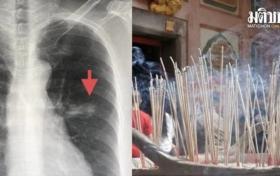

沒吸菸或吸入二手菸 泰婦連續六年燒香患肺癌

2022-09-20

11024